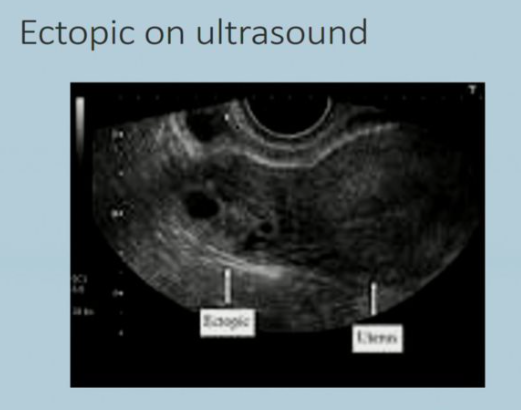

Usually around 7-8 weeks gestation, pts. will present with irregular bleeding or pain that concerns them of a miscarriage. When the pts. come in they will get a pregnancy test, which will be positive, and then an ultrasound, which will show an empty uterus

Might be worth getting an ultrasound to help locate the pregnancy and then: